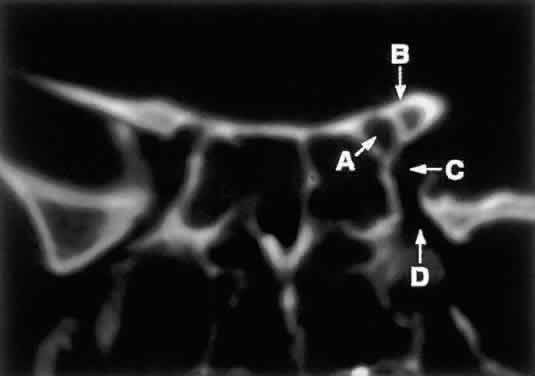

Fig. 8. Coronal CT image (bone window) of the orbital apex in a patient with facial trauma. Note the position of the posterior orbital foramina. The optic canal (A) is always seen in conjunction with the laterally adjacent anterior clinoid process (B) on both axial and coronal views. Slightly lower, the superior orbital fissure (C) communicates with the CS, found directly behind it. The inferior orbital fissure (D) provides communication through the orbital floor with the pterygopalatine fossa.

Finally, the sphenoid sinus abuts the orbital apex and is the last to pneumatize. Because of the proximity of the optic canal and CS (see Fig. 8), any sphenoid sinus pathology may manifest as a parasellar syndrome (discussed later). Pneumatization of the sphenoid sinus may extend into the anterior clinoid process, a variation of normal anatomy often encountered in orbital imaging studies.

FORAMINA AT THE ORBITAL APEX

The orbit is generally found to contain nine openings (Table 5). Only the optic foramen, SOF, and IOF will be discussed in detail (see Fig. 8). The optic foramen is located in the medial wall of the orbit in the body and lesser wing of the sphenoid bone. The optic canal is 4 to 10 mm long and 6.5 mm wide. On imaging studies, a 1-mm difference between canal diameters is considered clinically significant. The optic canal transmits the optic nerve, the ophthalmic artery, and the sympathetic innervation to the orbit. Note that sympathetic nerves also travel with the nasociliary nerve via the SOF.